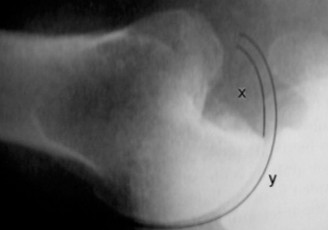

The correct answer is (C) (see Fig. 2–47). Humeral head impaction fractures involving less than 20% of the humeral head (Answers A, B) are often stable after open reduction and can do well with just a soft tissue procedure. Impaction fracture involving 20% to 40% (Answer C) frequently require an additional procedure to address the bony defect which may include disimpaction and bone grafting, allograft reconstruction, or infraspinatus/greater tuberosity transfer. Glenoid bone grafting may be needed as well, particularly if the glenoid bone loss is >20% to 25%.

Figure 2–47 The size of the humeral head defect can be calculated by dividing the arc of impaction (x) by the total articular surface arc (y).

Humeral head defects >40% (Answers D, E) frequently require a large allograft or prosthetic reconstruction. If a prosthetic option is chosen, some authors recommend placing the prosthetic glenoid component in 10 to 15 degrees of retroversion for an anterior dislocation and doing the opposite for a posterior dislocation. Objectives: Did you learn...?